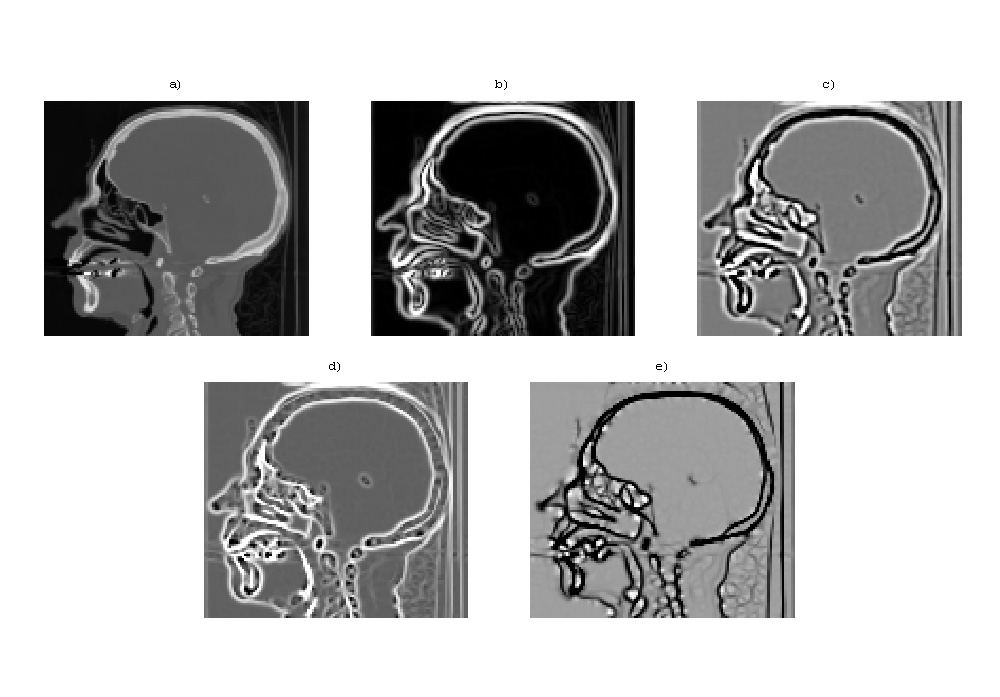

[Fig. 1] Figure 1: Property of 2D Eigenvalues images.

Images shown:

• a) Intensity

• b) gradient magnitude

• c) Laplacian

• d) the bigger eigenvalue

• e) the smaller eigenvalue The Laplacian (c) is a sum of the Hessian matrix eigenvalues (d) + (e). Eigenvalue images, however, can be thresholded leaving only salient features in the original image.

• [Fig. ++] Another 2D example, for a CT head

The same as above demonstrated for a CT image.